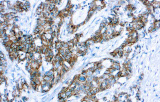

A imunohistoquímica (IHQ) com anticorpos primários CE/IVD é essencial para o diagnóstico e classificação precisos de malignidades ginecológicas e mamárias. Estes anticorpos permitem a deteção precisa de marcadores tumorais e proteínas celulares, apoiando o diagnóstico diferencial e guiando estratégias terapêuticas personalizadas.

Estudos recentes destacam o valor diagnóstico das proteínas do complexo SWI/SNF, particularmente ARID1B, na identificação de malignidades ginecológicas desdiferenciadas e indiferenciadas – tumores agressivos com mau prognóstico. A IHQ de ARID1B oferece elevada especificidade e está cada vez mais integrada em painéis diagnósticos para melhorar a precisão. Painéis com marcadores adicionais também apoiam a diferenciação de sarcomas uterinos, aumentando a exatidão diagnóstica. Evidência emergente sugere que ARID1B pode representar um alvo terapêutico potencial no carcinoma ovárico de células claras, embora as aplicações clínicas permaneçam em fase investigacional.

Anticorpos primários contra recetor de estrogénio (ER), recetor de progesterona (PR), HER2 e Ki-67 continuam a ser a pedra angular da classificação e decisões terapêuticas no cancro da mama. Estes anticorpos estão validados clinicamente e marcados CE/IVD para garantir deteção fiável e reproduzível de biomarcadores – crucial para orientar terapia hormonal e estratégias de tratamento direcionado.